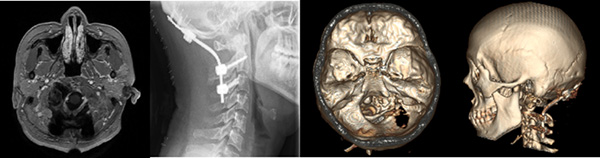

肿瘤被切除后,冯恩山及主治医师王小永对患者的枕颈部进行内固定,保证头部的稳定性。令人欣慰的是,手术过程中没有出现大出血、各分支血管及颅神经也都被完整地保留下来。

术后第二天,小兰已经可以下地活动和正常进食了,咳嗽反射也表现良好。术后复查头CT、MRI及颈部平片示术区无出血、肿瘤完整切除;枕颈固定装置位置及颈椎曲度均良好。